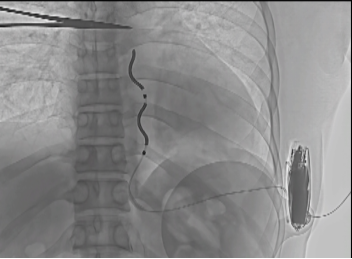

术后影像,EV-ICD成功者植入胸骨下

EV-ICD植入手术过程一切顺利,胸骨下除颤电极稳定,电学参数测试正常,诱颤测试成功转复。患者于次日转回普通病房,优化各项参数,恢复良好。